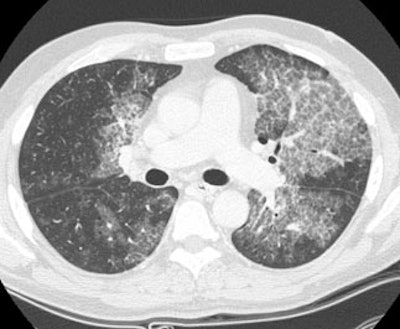

Alveolar Proteinosis:

The patient presented for evaluation of progressive shortness of breath. The CXR demonstrated bilateral perihilar infiltrates producing an appearance of pulmonary edema. HRCT exam revealed central areas of ground glass attenuation with underlying septal thickening producing a "crazy paving" appearance. Click images to enlarge.